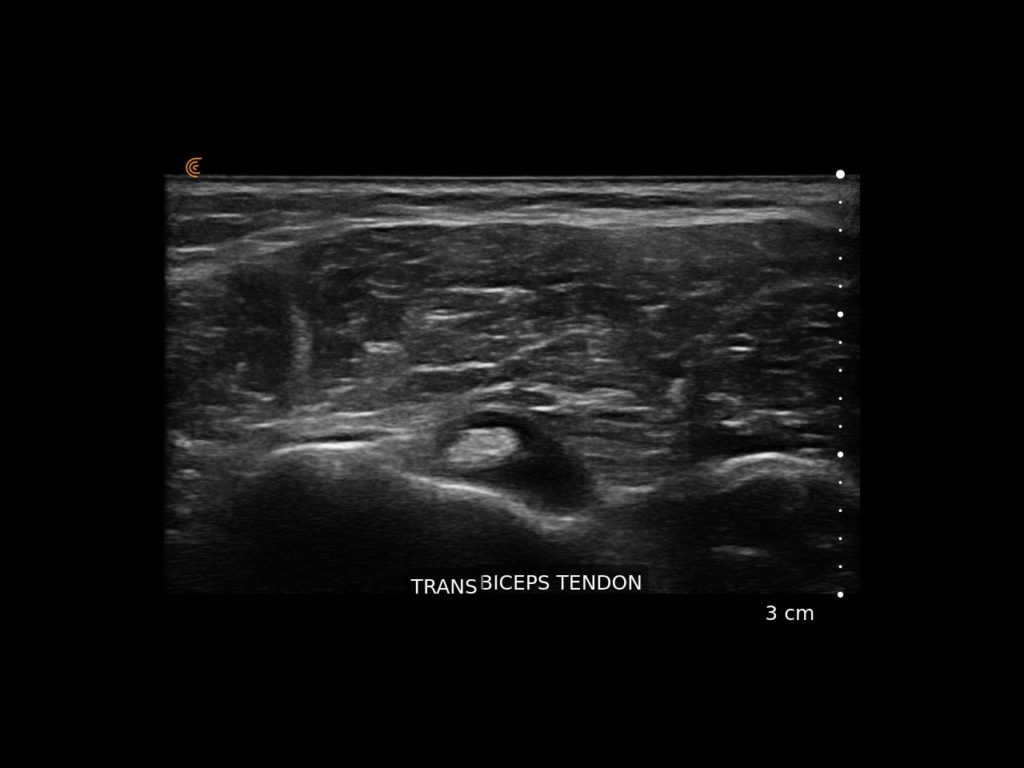

Elevate your sports medicine practice with high-definition dynamic imaging of muscles, joints, and tendons for accurate diagnostics and guided interventions on and off the field.

You can carry it from office to office, put it in your lab coat and use it on pain rounds. The image quality is superior.